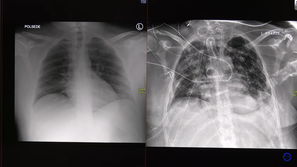

Rentgenska slika pljuč

UKC Ljubljana

Video: Strašljive posledice, ki jih povzroči covid-19

Dva primera covid pljučnice - pri enem bolniku se je stanje relativno hitro izboljšalo, drugemu, le 30-letnemu bolniku,…